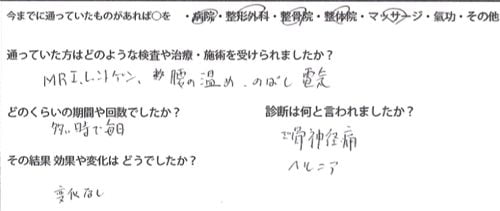

今までの治療履歴

今までの治療歴はこんな感じで

病院や整形外科・整骨院・整体院・マッサージなどに行きMRIやレントゲンの検査を繰り返し

マッサージや腰の牽引 温めたり 電気をかけたり効果があると思うものを北海道から沖縄まで行ってありとあらゆるものを試して

治療費総額100万円以上かかったそうなのですが全く変化が無かったそうです。